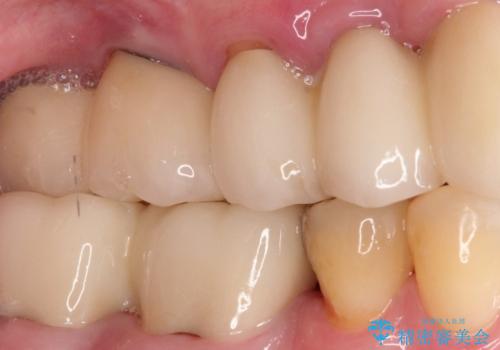

【PGAインレー】深い位置の二次カリエス

- 定期検診にて虫歯を発見したため、PGAインレーにて治療を行いました。

PGAインレーは金と白金を多く含み、精度高い修復が可能です。